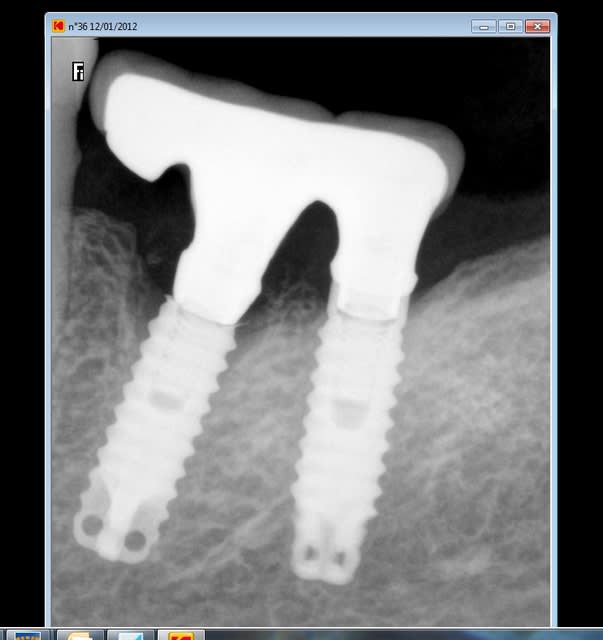

12/01/2012 à 18h22

comme j'ai la chance que les patients fassent le suivi

rvg en 2011

pseudo réossification autour de mon bricolage si on fait attention faut dire que c'est un beau cône morse (!)

--

Euh je ne veux pas être négatif mais je dirai plutôt une cratérisation établie; ton os arrivait à la spire distal n°10 (à l'origine) maintenant il est bien en dessous :-(

Désolé mais effectivement c'est une très belle gestion de complication, je te félicite pour celà même si je ne partage pas ton optimisme "osseux".

pourquoi penses tu que je parle de "pseudo" réossification et de cone morse : aucune étanchéité autour du bricolage qui présente encore moins d'étanchéité qu'un connectique à plat

les contraintes que montraient Haig sont bien toujours présentes même si soulagées par le fait que l'on ait "acastillé" l'autre coté .

il s'agit d'un sauvetage la corticale en linguale est toujours présente mais poche en vestibulaire car l'axe de cet implant n'est pas non plus idéal en vestibulo lingual comme mésio distal ya pas de raison:-))